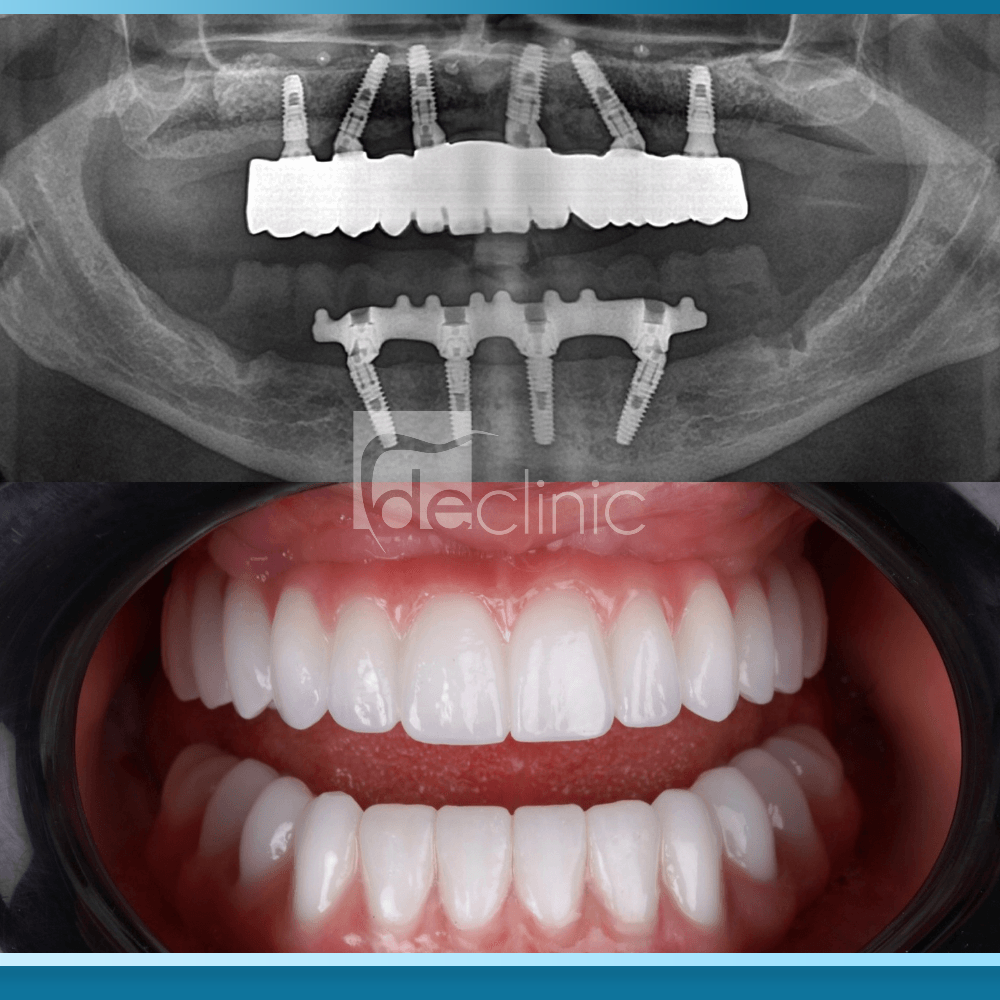

Kỹ thuật All on 6 là giải pháp phục hình răng toàn hàm cố định hiện đại, sử dụng sáu trụ Implant bằng Titanium cấy ghép vào xương hàm để nâng đỡ một cầu răng sứ gồm 12 đến 14 răng. Các trụ này đóng vai trò như những chân răng nhân tạo, sau quá trình tích hợp xương (Osseointegration) – hiện tượng các tế bào xương bám chặt vào bề mặt Implant – chúng tạo thành một khối thống nhất và vững chắc.

Theo các báo cáo từ Liên đoàn Nha khoa Thế giới (FDI), All on 6 được thiết kế để chịu tải trọng lớn, cho phép phân bổ lực nhai đều khắp cung hàm, đặc biệt phù hợp cho những trường hợp mất răng lâu năm dẫn đến tiêu xương diện rộng ở người trung niên.

Mặc dù có chi phí cao hơn, All on 6 vẫn được giới chuyên môn coi là tiêu chuẩn vàng trong phục hình toàn hàm cho đối tượng trung niên nhờ tính ổn định lâu dài và khả năng bảo tồn cấu trúc khuôn mặt. Sự hiện diện của sáu trụ Implant phân bổ đều trên cung hàm không chỉ giúp ăn nhai ngon miệng mà còn ngăn chặn triệt để tình trạng tiêu xương hàm – nguyên nhân chính gây ra hiện tượng móm và lão hóa sớm.

Hơn nữa, xét về mặt cơ học y khoa, All on 6 chia nhỏ áp lực lên nhiều điểm tựa hơn, giúp giảm tải trọng cho từng trụ Implant riêng lẻ.

Điều này đặc biệt quan trọng đối với những người có lực nhai mạnh hoặc có thói quen nghiến răng. Theo các nghiên cứu trên tạp chí JADA (Journal of the American Dental Association), tỷ lệ thành công sau 10 năm của All on 6 cao hơn so với các loại hàm phủ chỉ có 2 trụ.